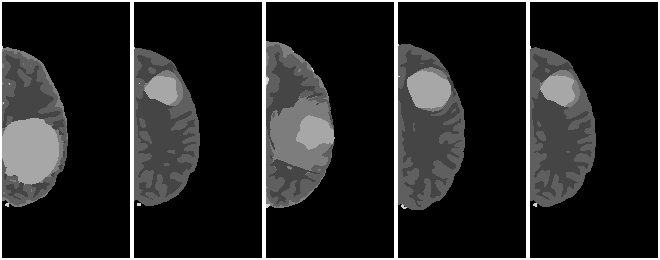

Sample Flair Images

| Tumor | NoTumor |